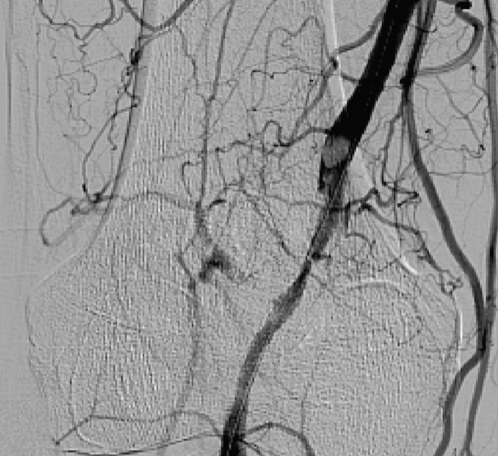

A 60-year-old male initially presented with complaints of a non-healing wound on his right shin, right leg claudication walking 10-15 minutes, and an ankle-brachial index of 0.40. He underwent lower-extremity angiography. Initial angiogram showed a 100% occlusion of the right superficial femoral artery (SFA) at the level of Hunter’s canal with reconstitution at the distal popliteal artery (Figure 1). With the exception of slow-flow, the remainder of his lower-extremity arteries were angiographically normal. This lesion was thought to be thrombotic; he underwent AngioJet thrombectomy (Boston Scientific) and percutaneous transluminal angioplasty (PTA) with suboptimal results (Figure 2). A 6 x 80 mm Supera stent (Abbott Vascular) was deployed at the lesion (Figure 3).

ACD is characterized by the development of mucus-containing cysts, most commonly in the popliteal artery, causing partial or complete obstruction of blood flow. Clues in this patient’s prior angiogram point to ACD as the diagnosis. First, it is unusual to have severe peripheral vascular disease causing occlusion of the popliteal artery, without evidence of disease affecting other lower-extremity arteries. Additionally, after PTA of the popliteal, angiogram showed a smooth, well-defined, filling defect characteristic of ACD (Figure 2). On closer examination of the angiogram, cysts can be visualized (Figure 5). Definitive diagnosis of ACD can be made with computed tomographic or magnetic resonance angiography. Treatment options include cyst aspiration or excision, which are often ineffective due to cyst regrowth, and bypass of the affected artery. The affected artery should not be stented. ACD exacerbated the mechanical forces on the stent during movement, contributing to fracture. Our patient was referred for right femoral-popliteal bypass. Histopathology confirmed ACD. He is doing well at 6-month follow-up.